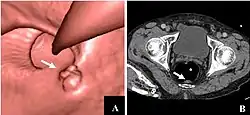

CT colonography of a rectal mass. Left image is a volume rendering and right image is a thin slice. It also shows the rectal tube used for insufflation of gas to distend the colon. | |